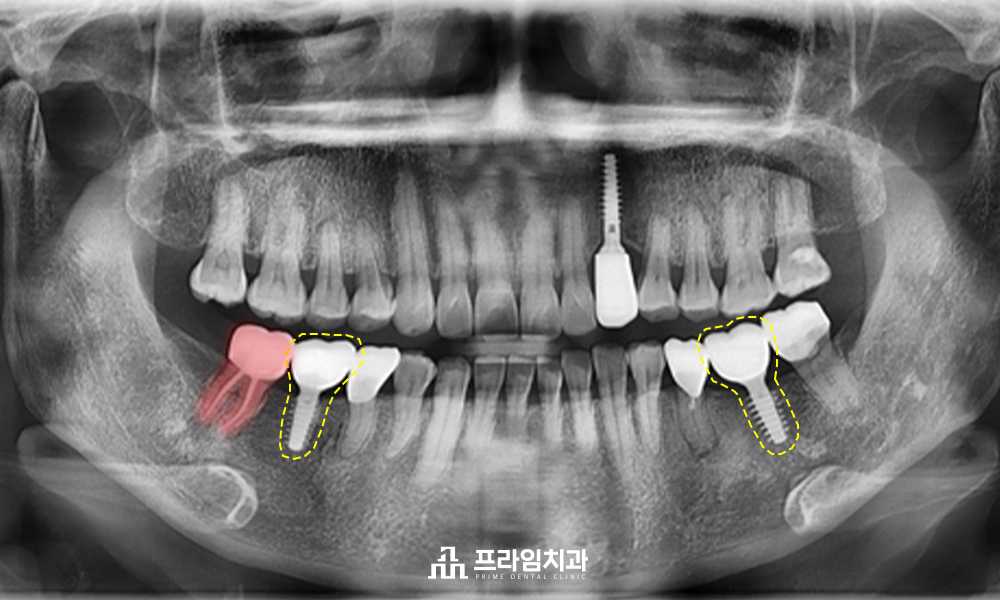

보통은 치아를 살려 쓰기 힘든 경우, 발치를 진행한 후 임플란트를 식립하시는 분들이 대부분입니다. 하지만 환자분의 경우에는 왼쪽 아래 맨 끝의 사랑니의 상태가 괜찮았으며, 뿌리가 휘어지지 않아 충분히 살려 사용할 수 있어 상태가 좋지 않은 오른쪽 아래 두 번째 큰어금니 발치 후 사랑니 자가치아이식술을 통해 회복하는 것으로 하였습니다. 환자분께서는 관리가 어려워 브릿지 크라운으로 치료를 다시 하지 않고 임플란트 식립을 원하셨습니다. 따라서 염증이 존재하는 왼쪽 아래 두 번째 작은 어금니는 염증을 해소하는 치료를 진행하며, 왼쪽 아래 첫 번째 큰 어금니와 오른쪽 아래 첫 번째 큰 어금니는 임플란트 식립을 진행하는 것으로 하였습니다.

자가치아이식술이란 말 그대로 자신의 치아를 옮겨 심어 자연치아를 사용하는 방법입니다. 보통 환자분처럼 치아우식증이 심하거나 치주 질환으로 인해 발치해야 할 때, 주변의 온전한 사랑니를 이용하는 경우가 많습니다. 자가치아이식술 치료는 살리기 힘든 치아를 먼저 발치한 후 옮겨 심을 사랑니를 조심스럽게 발치하게 됩니다. 사랑니는 치아 뿌리 끝을 자르고 처치를 진행한 후 옮겨 심고, 어느 정도 자리를 잡은 후 다시 염증이 생기지 않도록 신경치료를 진행합니다. 신경치료 후에는 치아를 보호하기 위해 크라운을 씌워 마무리하게 됩니다.